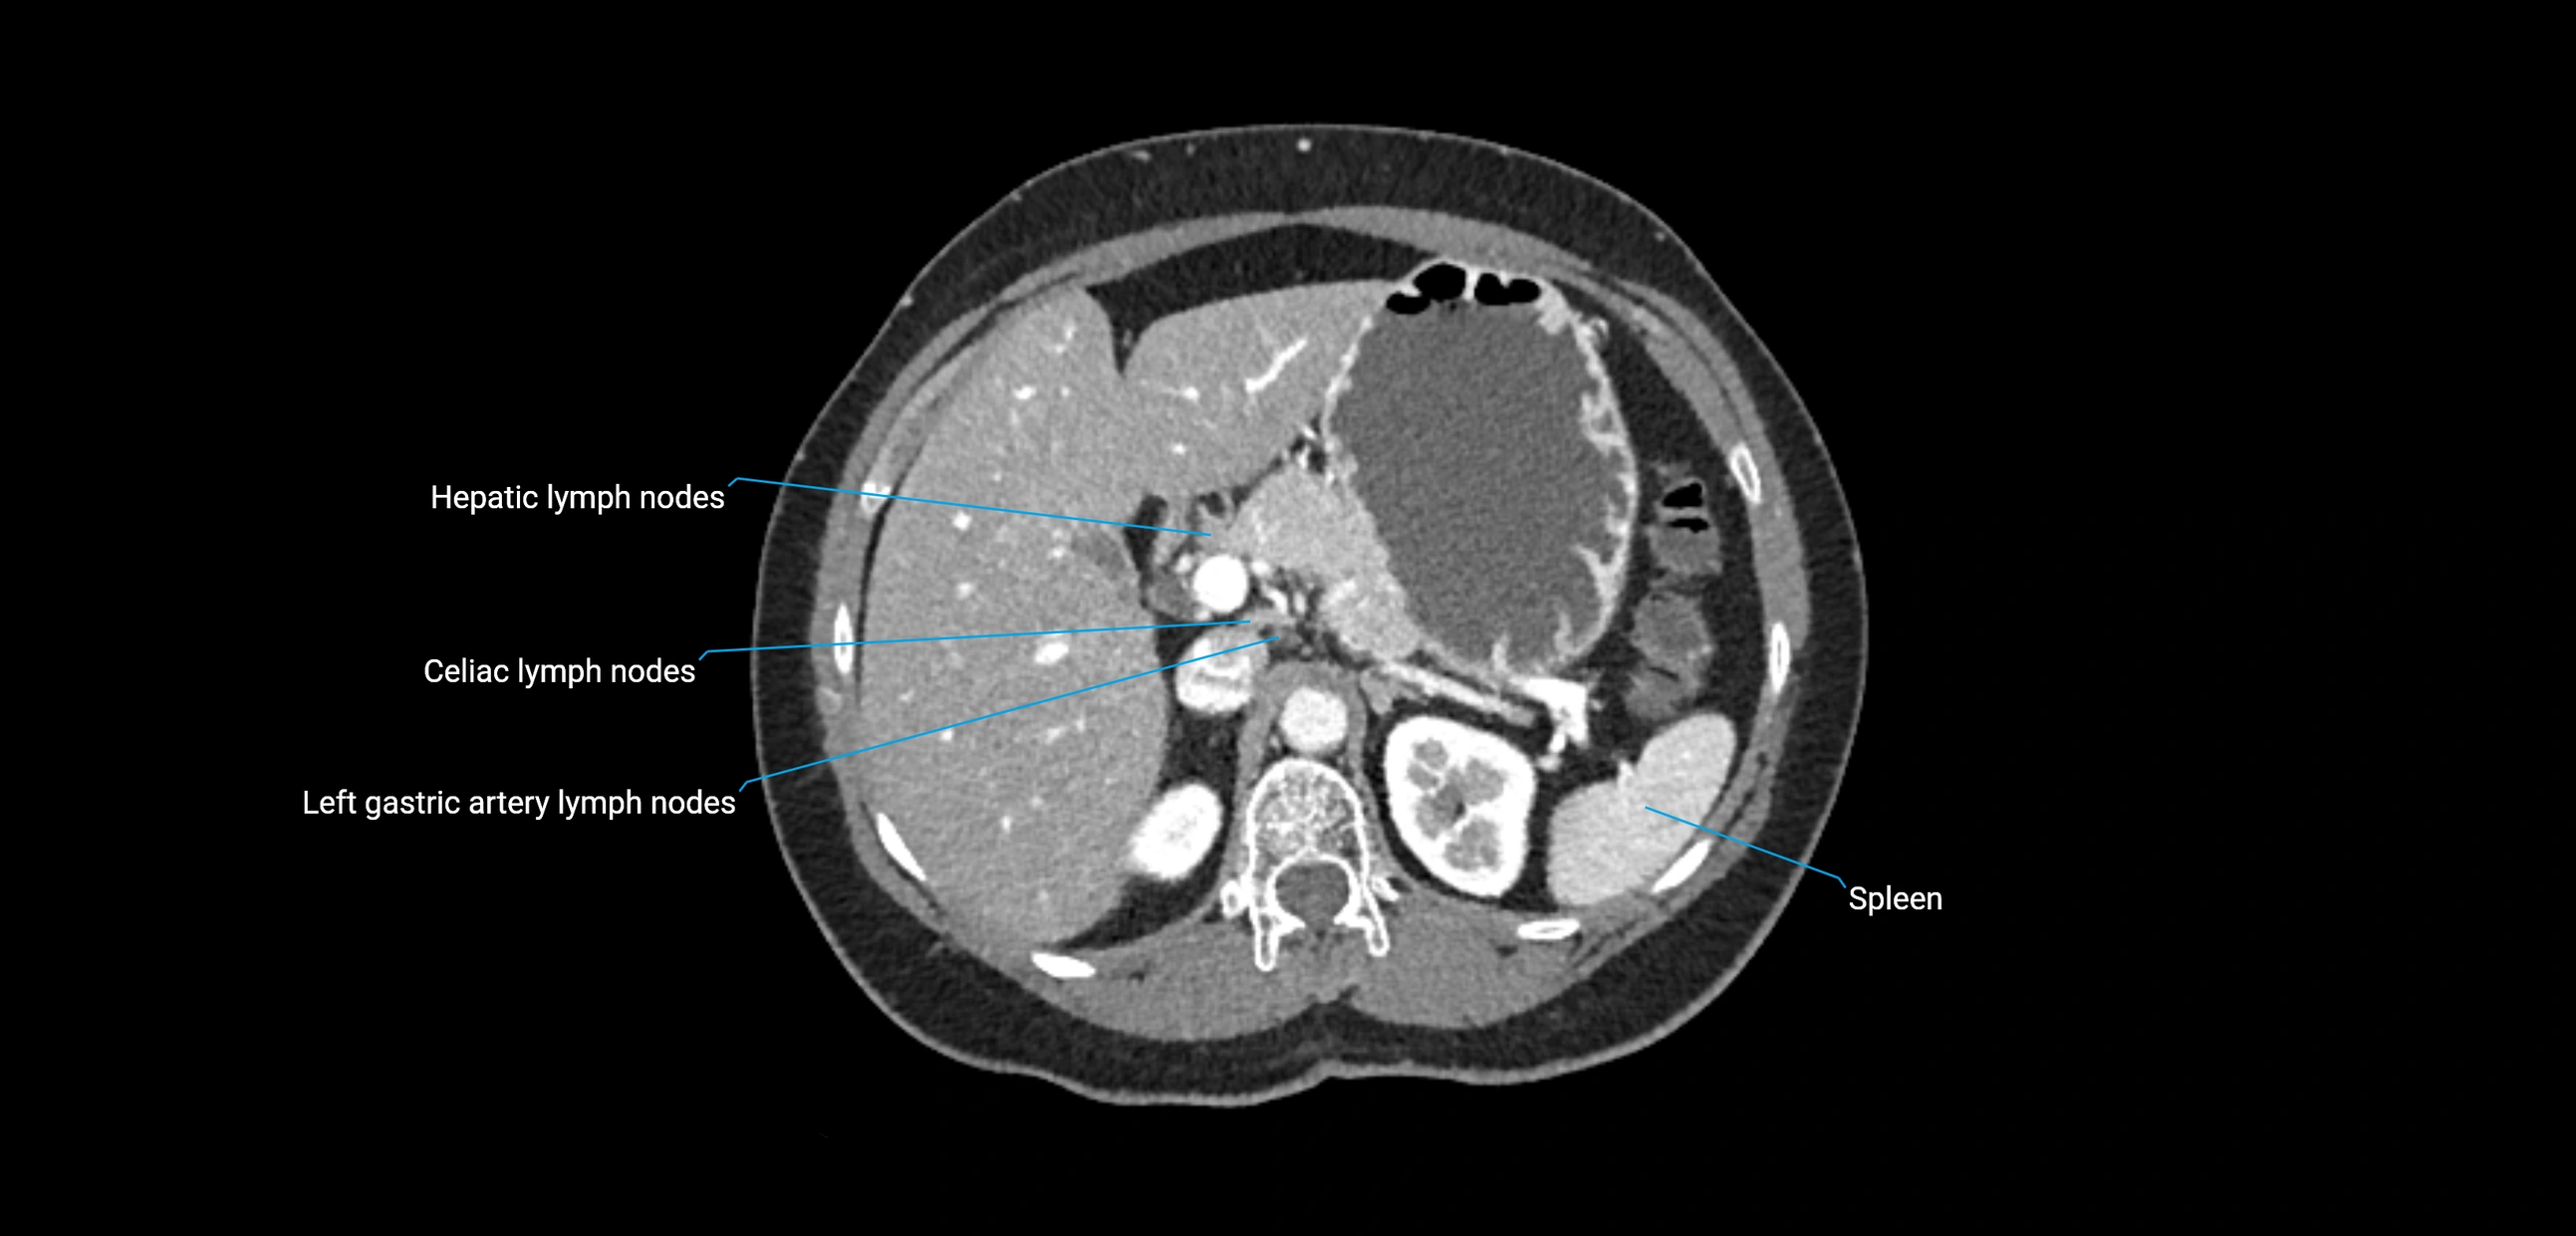

CT Appearance

CT Pre-Contrast:

• Nodes appear as soft-tissue density nodules adjacent to the aorta and IVC

• Calcification may be seen in chronic infections (e.g., tuberculosis)

CT Post-Contrast:

• Normal nodes enhance homogeneously

• Malignant nodes may show heterogeneous enhancement, central necrosis, or conglomerate formation

• Size >1 cm short axis is suspicious, though morphology and distribution are equally important

CT Venography (CTV):

• Demonstrates nodal encasement or compression of adjacent vessels (aorta, IVC, renal veins)

• Useful in staging testicular and ovarian malignancies

• Provides 3D reconstructions for retroperitoneal lymph node dissection planning